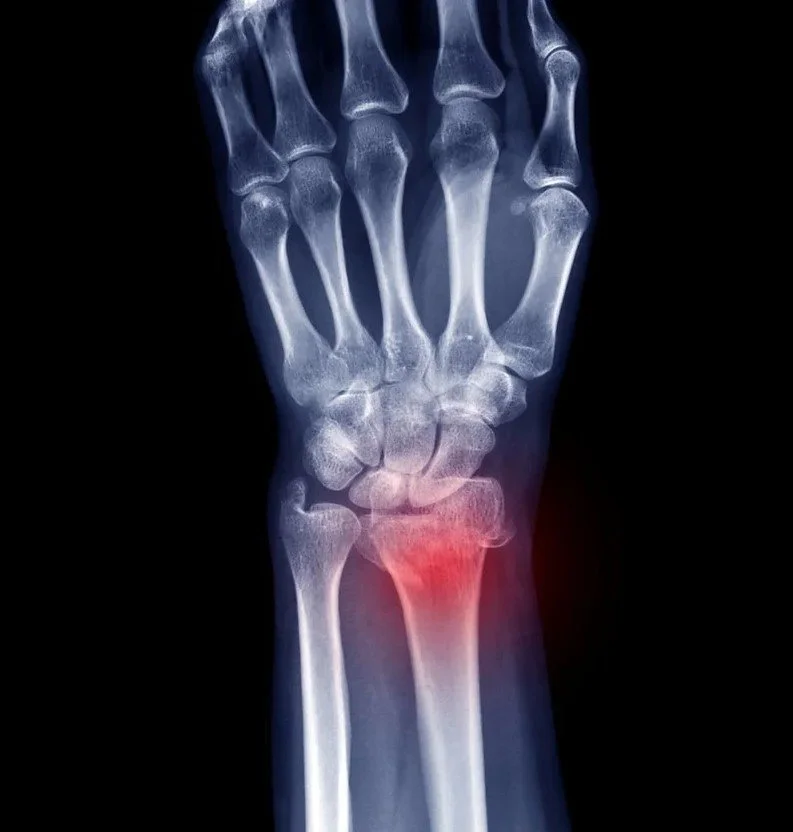

Κάταγμα Πηχεοκαρπικής / Κερκίδας

Το κάταγμα πηχεοκαρπικής ή κερκίδας (καρπός), είναι το πιο συχνό κάταγμα στους ενήλικες. Εμφανίζεται τρεις φορές συχνότερα στις γυναίκες, κυρίως λόγω οστεοπόρωσης. Ο συνηθέστερος λόγος τραυματισμού είναι η πτώση σε τεντωμένο χέρι.

Η αντιμετώπιση μπορεί να είναι συντηρητική ή χειρουργική. Εάν το κάταγμα δεν έχει μετατοπιστεί, εφαρμόζεται γύψος για έξι εβδομάδες, ακολουθούμενος από νάρθηκα. Μετά την αφαίρεσή του, η φυσικοθεραπεία αποκαθιστά τη λειτουργικότητα του καρπού. Η χειρουργική επέμβαση είναι απαραίτητη σε ασταθή ή ενδαρθρικά κατάγματα. Χρησιμοποιούμε πλάκα και βίδες για να συγκρατήσουμε τα οστά (ORIF). Η αφαίρεσή των υλικών γίνεται μόνο εάν προκαλούν ενόχληση.